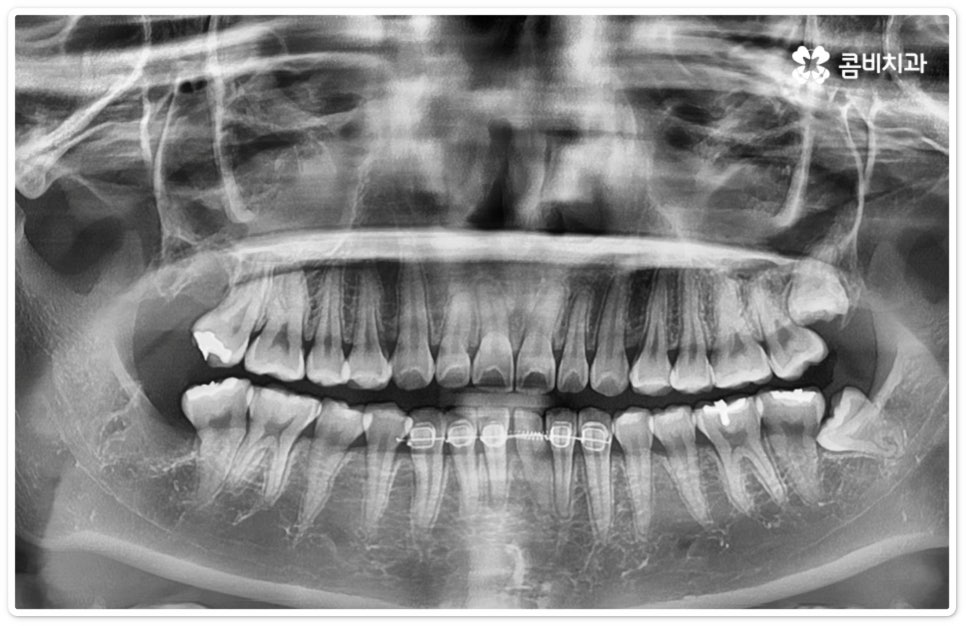

사랑니의 개수, 위치, 각도나 뿌리의 형태, 매복 깊이 등은 사람마다 다른데 그 중에서 특히 완전히 매복된 상태로 비스듬히 누운 채 자리잡은 아래 사랑니의 경우 턱을 가로지르는 하치조 신경과 가깝기 때문에 누운사랑니발치 시 신중을 기하지 않으면 혹시 모를 부작용인 감각 이상을 초래할 수 있으므로 뛰어난 해부학적 지식과 풍부한 임상 경험, 세심한 기술력을 가지고 있는 숙련된 의료진에게 치료를 받으시길 권유드리고 있어요. 혹시라도 신경 손상이 발생하게 되면 입술이나 턱이 마취된 듯 침이 흘러도 감각이 없거나 양치질을 할 때 물이 입술밖으로 세어나가는 상태가 유발될 수 있으니 조심해야 할 거예요.

우리나라 사람 중에 약 7% 정도는 사랑니가 아예 없다고 하지만 보통 25세가 지났는데 사랑니가 나오지 않았다면 매복 사랑니이거나 누워있는 사랑니인 경우가 많으므로 정밀 검진을 받아보실 필요가 있는데요. 이때 염증을 지속적으로 유발하거나 음식물이 끼면서 관리가 잘 안 되면서 발생하는 충치 등 좋지 않은 영향을 주고 있다면 발치 처치를 해 주는 게 좋은데, 20대에 누운사랑니발치 를 진행하는 것이 40대 이후에 하는 것보다 통증 및 출혈도 덜하고 회복도 빠를 수 있으니 이를 염두에 두시길 바라고 있어요.

특히 40세 이상 성인분들의 경우 치아의 긴 뿌리가 완전하게 형성이 되어 있어 치근 유착이 심한 케이스가 있을 수 있으며 대부분 연령이 증가할수록 사랑니 주위 뼈가 단단해지고 탄력성이 감소하는 경향을 보이기 때문에 상황에 따라 무리하게 매복된 뿌리까지 발치할 경우 턱뼈가 부러지거나 신경이 손상되는 등의 합병증 위험이 증가하는 케이스에서는 치아 뿌리는 남긴 채 사랑니의 머리 부분만 잘라서 빼내는 치관절제술을 시행해야 할 수도 있는데요. 이런 경우 약 14%81%는 치관절제술 후 치아 뿌리가 상방으로 움직여서 잇몸 밖으로 노출이 되기 때문에 다시 치근을 제거하는 수술을 해주게 되는데, 환자분들의 입장에서는 수술을 두 번에 걸쳐 하기 때문에 거부감이 들 수 있으나 하치조 신경과의 거리를 벌린 후 완전히 제거하는 것이 통증 및 감염의 위험을 줄이는 보다 안전한 방법이므로 치관절제술 후 1달1년 정도의 시간을 두고 3D CT 촬영을 통해 다시 위치를 꼼꼼하게 확인한 후 치료 받으시길 권유드리고 있어요.

매복 형태의 사랑니는 잇몸을 절개하고 발치해야 하며, 특히 깊숙하게 누운사랑니발치 시에는 신경을 건드리지 않도록 사랑니를 조각내어 조심해서 빼내야 할 뿐 아니라 환자분들의 상태에 따라 잇몸뼈를 조금씩 삭제해야 할 수도 있기 때문에 이러한 고난도 시술에는 주변 조직의 손상을 최소화하고 혹시 모를 부작용의 위험을 줄이며 출혈 및 통증이 커지지 않도록 하기 위해서 시술자의 높은 숙련도가 더욱 요구된다고 할 수 있어요. 또한 매복된 사랑니의 각도, 뿌리 형태, 인접 치아와의 관계, 신경 위치 등을 정확하게 파악하고 체계적인 맞춤 계획을 세워 무리하지 않게 사랑니 발치 수술을 진행하기 위해서 정밀 진단이 가능한 3D CT 장비가 있는 치과에서 꼼꼼한 검사부터 받아보는 것이 중요할 거예요.